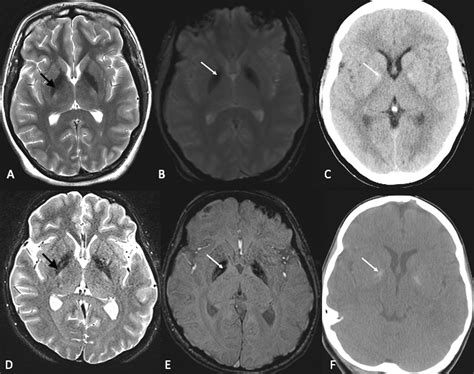

• Neuroimaging: Using advanced imaging techniques to study brain structure and function in individuals with the disorder.